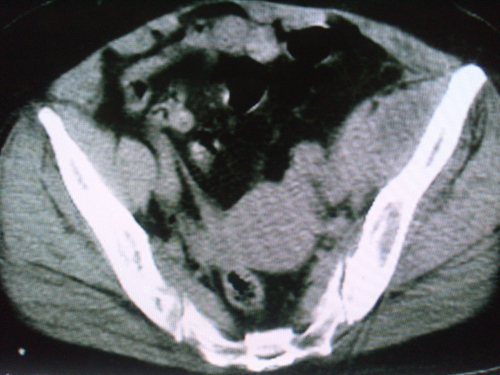

标题: CT18663:女 58岁 左髂区庝痛一年余,加重两月 [打印本页]

标题: CT18663:女 58岁 左髂区庝痛一年余,加重两月

左髂翼内前方软组织样肿块,其密度不均匀,内部呈略低密度的改变,肿块边界清楚,呈宽基底与髂骨“接触”,髂骨骨质破坏。未见明显骨膜反应性增生,及骨旁瘤骨存在。病变不侵犯同侧骶髂关节。

考虑----1 纤维肉瘤-----年龄、表现符合,病变为低度恶性。  或    2  转移瘤-----为髂骨发病率第一病变,需警惕。

左侧髂內肌明显肿大,密度稍不均,可见略低密度的改变,其边界清楚,与髂腰肌间脂肪间隙清晰,与髂骨呈宽基底“接触”,髂骨骨质膨胀性破坏。

考虑左侧髂內肌恶性肿物,建议病检确诊。